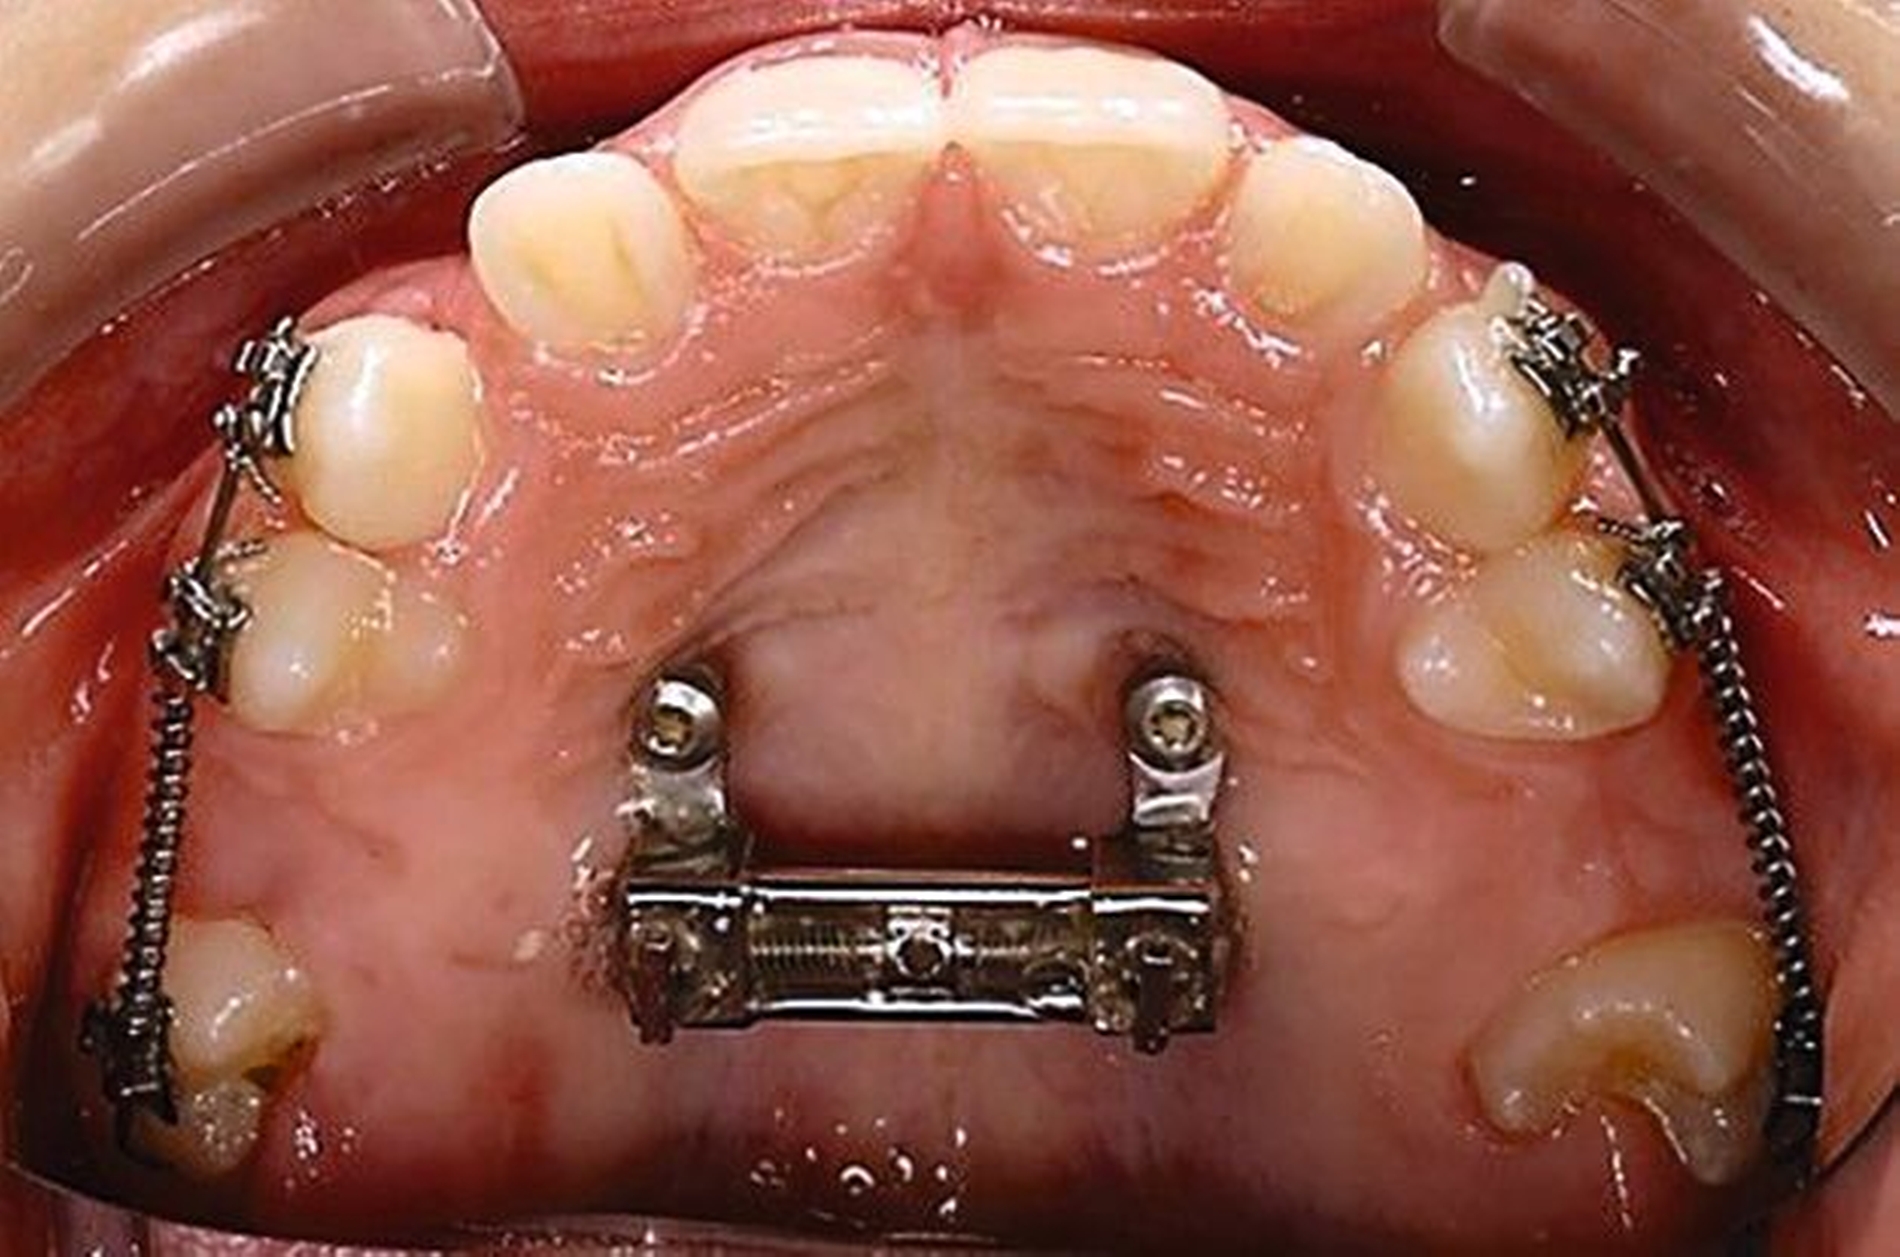

Für die Zähne 13, 16, 23 und 26 wurde eine weitere chirurgische Freilegung durchgeführt. Zwei Kragarme (0,017 x 0,025 Zoll TMA-Draht, Dentaurum, Ispringen, Deutschland) wurden verwendet, um die Zähne 13 und 23 kieferorthopädisch in den Zahnbogen einzustellen. Danach wurde eine Teil-Multi-Bracket-Apparatur eingesetzt, um die eruptierten Zähne zu nivellieren (Abbildung 5b). Nach einer Behandlungsdauer von circa sechs Monaten waren die chirurgisch freigelegten Zähne optimal eingeordnet (Abbildungen 5c und 5d). Um die Lücke für die noch retinierten Prämolaren 15 und 25 zu öffnen, wurden in dieser Region auf den Teilbögen offene Federn angebracht. Danach wurden die Zähne 15 und 25 chirurgisch freigelegt und ebenfalls mithilfe von zwei Kragarmen (0,017 x 0,025 Zoll TMA-Draht) eingestellt (Abbildungen 5e und 5f, Abbildung 6).